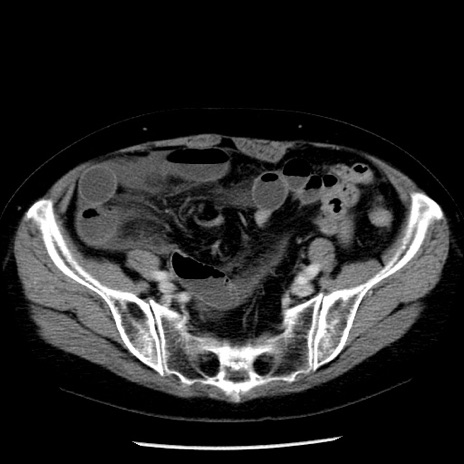

症例13(横断像)

【症例】70歳代女性

【主訴】腹痛、嘔吐

【現病歴】15時間程前(昨晩)より腹痛あり。今朝になっても症状の改善なく、嘔吐あり。腹痛も増悪あり、救急外来受診。

【既往歴】子宮癌全摘術後

【身体所見】意識清明、BP 121/72mmHg、P 74bpm、SpO2 100%(RA)、腹部:平坦・軟、腸雑音ほぼ聴取せず。下腹部・心窩部・臍左上に圧痛あり。反跳痛なし。

【データ】WBC 10600、CRP 0.15